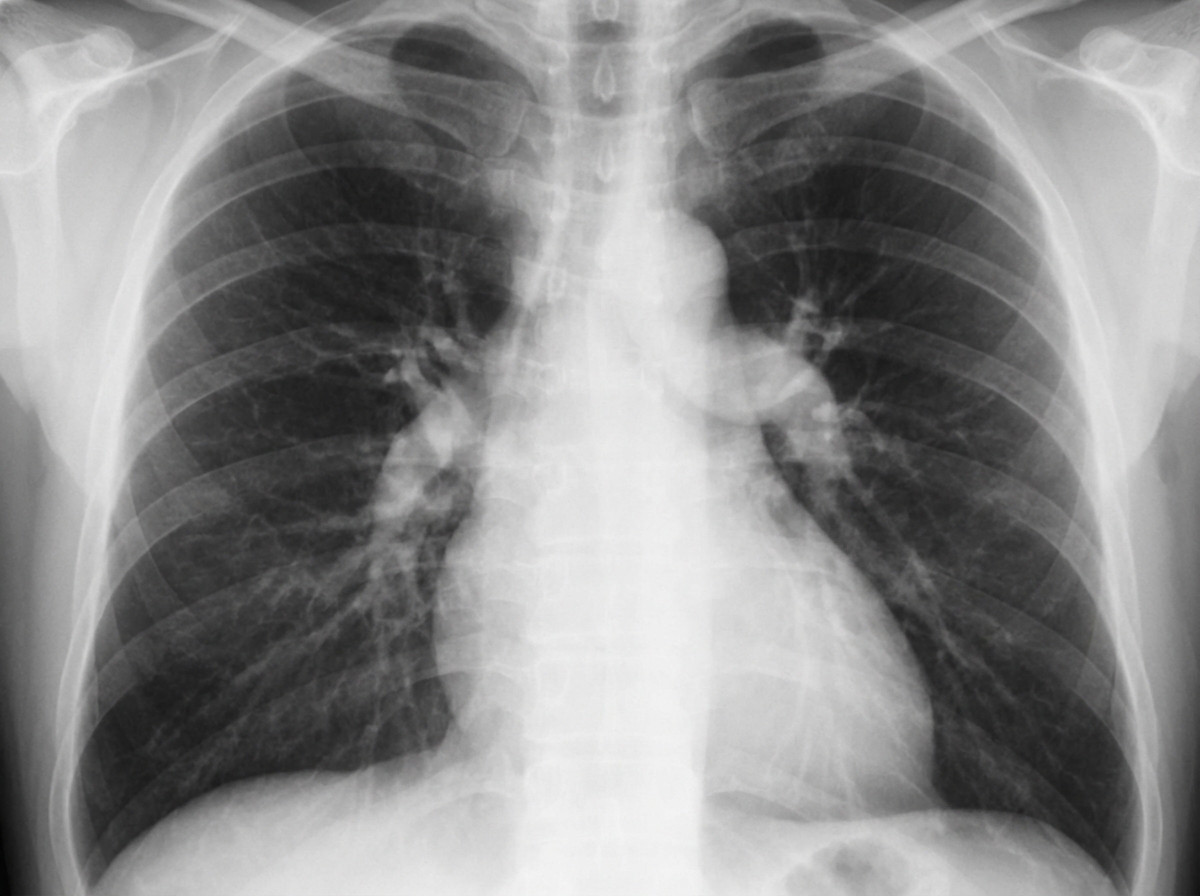

A 24-year-old female graduate student reports increasing shortness of breath with exercise and has recently noticed dyspnea on mild activity. One day before presenting at the office, she experienced sudden loss of consciousness while shopping at a grocery store. On physical examination, vital signs are: pulse 88 bpm; temperature 97.8degF; respirations 18/min; blood pressure 100/70 mm Hg. BMI is 34. ABGs on RA: pH 7.43; PCO2 36 mm Hg; PO2 87 mm Hg. Chest x-rays are shown. What clinical and chest radiographic diagnosis may be commonly associated with this presentation?

Explanation: ***A loud P2 on cardiac auscultation*** - **Pulmonary arterial hypertension (PAH)** commonly presents in young women with exertional dyspnea, syncope, and **loud P2** (pulmonary component of S2) due to increased pulmonary pressures. - The presentation of a **young obese female** with progressive dyspnea and syncope, along with **prominent pulmonary arteries** on chest X-ray, strongly suggests PAH with accentuated P2. *A loud A2 on cardiac auscultation* - **Loud A2** (aortic component of S2) is associated with **systemic hypertension**, not pulmonary hypertension. - This patient has **normal blood pressure** (100/70 mmHg), making systemic hypertension unlikely. *Right arm swelling* - **Unilateral arm swelling** suggests **superior vena cava syndrome** or **deep vein thrombosis**, not related to this presentation. - PAH typically causes **bilateral lower extremity edema** in advanced stages, not unilateral upper extremity swelling. *Rib notching* - **Rib notching** is a radiographic finding associated with **coarctation of the aorta** due to collateral circulation development. - This patient's presentation with **exertional dyspnea** and **syncope** is not consistent with aortic coarctation, which typically presents with hypertension.